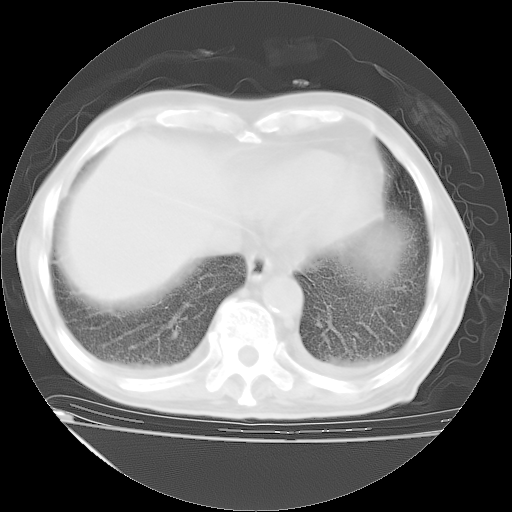

经过24天治疗,岳父的病情基本稳定。生活基本可以自理,可以下床活动。呼吸困难早已消失。体温基本正常。

只是甲强龙用80mg时血小板升到正常,改为60mg后又降到63×10*9/L。

主要治疗甲强龙80mg×14天,60mg×10天;同时抗结核(异烟肼+利福平+乙胺丁醇)。环磷酰胺0.1 tid 10天。

特别感谢胡教授、高管、桃子版主给出关键的治疗建议。桃版把所有肺部影像和全部临床资料请所在医院呼吸科、感染病科、结核科、临床免疫科专家会诊。临床免疫科专家制定了完整的治疗方案。